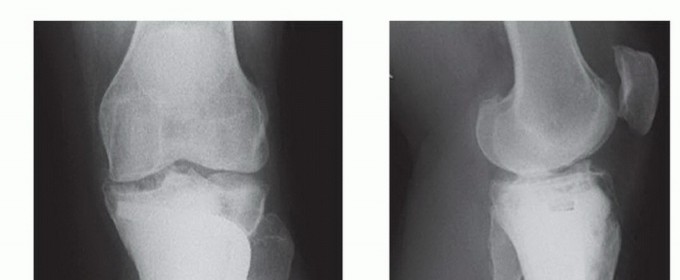

- ورم الخلايا العملاقة (Giant Cell Tumor): قد يكون حميدًا ولكنه يمكن أن يكون عدوانيًا موضعيًا وقد يتكرر.

الأعراض والعلامات التحذيرية لأورام العظام

التشخيص المبكر لأورام العظام، سواء كانت حميدة أو خبيثة، يلعب دورًا حاسمًا في نجاح العلاج والحفاظ على جودة حياة المريض. لذا، من المهم جدًا الانتباه إلى أي أعراض غير عادية قد تشير إلى وجود ورم. تختلف الأعراض بناءً على نوع الورم، حجمه، موقعه، وما إذا كان قد انتشر.

التورم أو الكتلة الملموسة:

- الظهور: قد يظهر تورم أو كتلة صلبة في المنطقة المصابة من العظم.

- الحجم: قد تكون هذه الكتلة مرئية أو يمكن الشعور بها تحت الجلد.

الكسور غير المبررة (الكسور المرضية):

- السبب: قد يؤدي الورم إلى إضعاف العظم، مما يجعله عرضة للكسر حتى مع إصابة طفيفة أو بدون سبب واضح.

يتوقف اختيار العلاج المناسب لأورام العظام على عدة عوامل، منها نوع الورم (حميد أم خبيث)، حجمه، موقعه، مدى انتشاره، عمر المريض وصحته العامة، وتفضيلات المريض. يهدف العلاج بشكل عام إلى استئصال الورم بالكامل، وتخفيف الأعراض، ومنع تكرار الورم، والحفاظ على وظيفة الطرف المصاب قدر الإمكان.

الاستئصال الواسع (Wide Excision):

إزالة الورم مع هامش واسع من الأنسجة السليمة المحيطة لضمان إزالة جميع الخلايا السرطانية. قد يتطلب ذلك إعادة بناء العظم باستخدام طعوم عظمية أو بدائل صناعية.